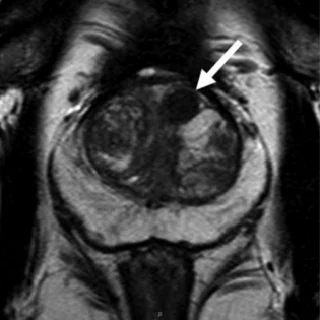

Вытянутой формы или не ограниченная гипоинтенсивная гомогенная зона, менее 1.5см

То же что и PIRADS 4, только размером более 1.5см или с распространением за пределы простаты